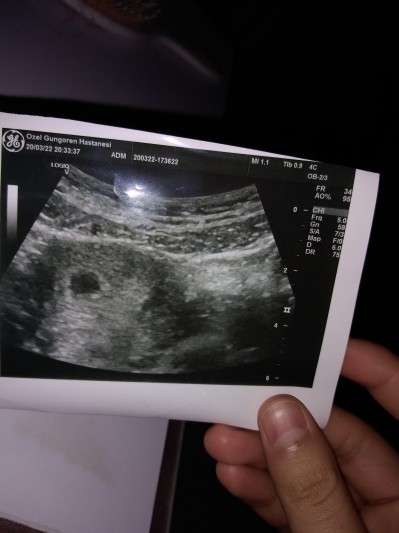

Arkadaşlar ben geçen keseyi gördüm ultrason fotoğrafinin üzerindeki yazıları anlamadım bilen varsa bakabilir mi bide benim gibi keseyi görüp bebeği göremeyen arkadaşlarda ultrason fotoğrafini atarsa karsilastirirsam biraz merakım diner teşekkür ederim hepinize

Gebelik haftası 6+1

Fotoğraf bu arkadaşlar

image

Kese oluşmuş inşallah haftaya bebekte gözükür canım sağlıcakla al kucağına benimde iki kürtajım var sonra hemen hamile kaldım stres yapma

Ben 5 +4 günlükken gıtmsdım  kese var bebel cok kucuk oldugu ıcın kenarda tutunma aşamasında demısdı 8 haftalıkken gıttım kalp atısını gordum bebegım bırazdaha netlesmısdı suan 11+6 yız

Bebek varsa da daha nokta kadar olduğu için görünmüyor bne de 6da gittim 8de göründü bebek

6+4 iken kese boyleydi bizde